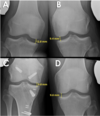

Hva viser disse bildene oss?